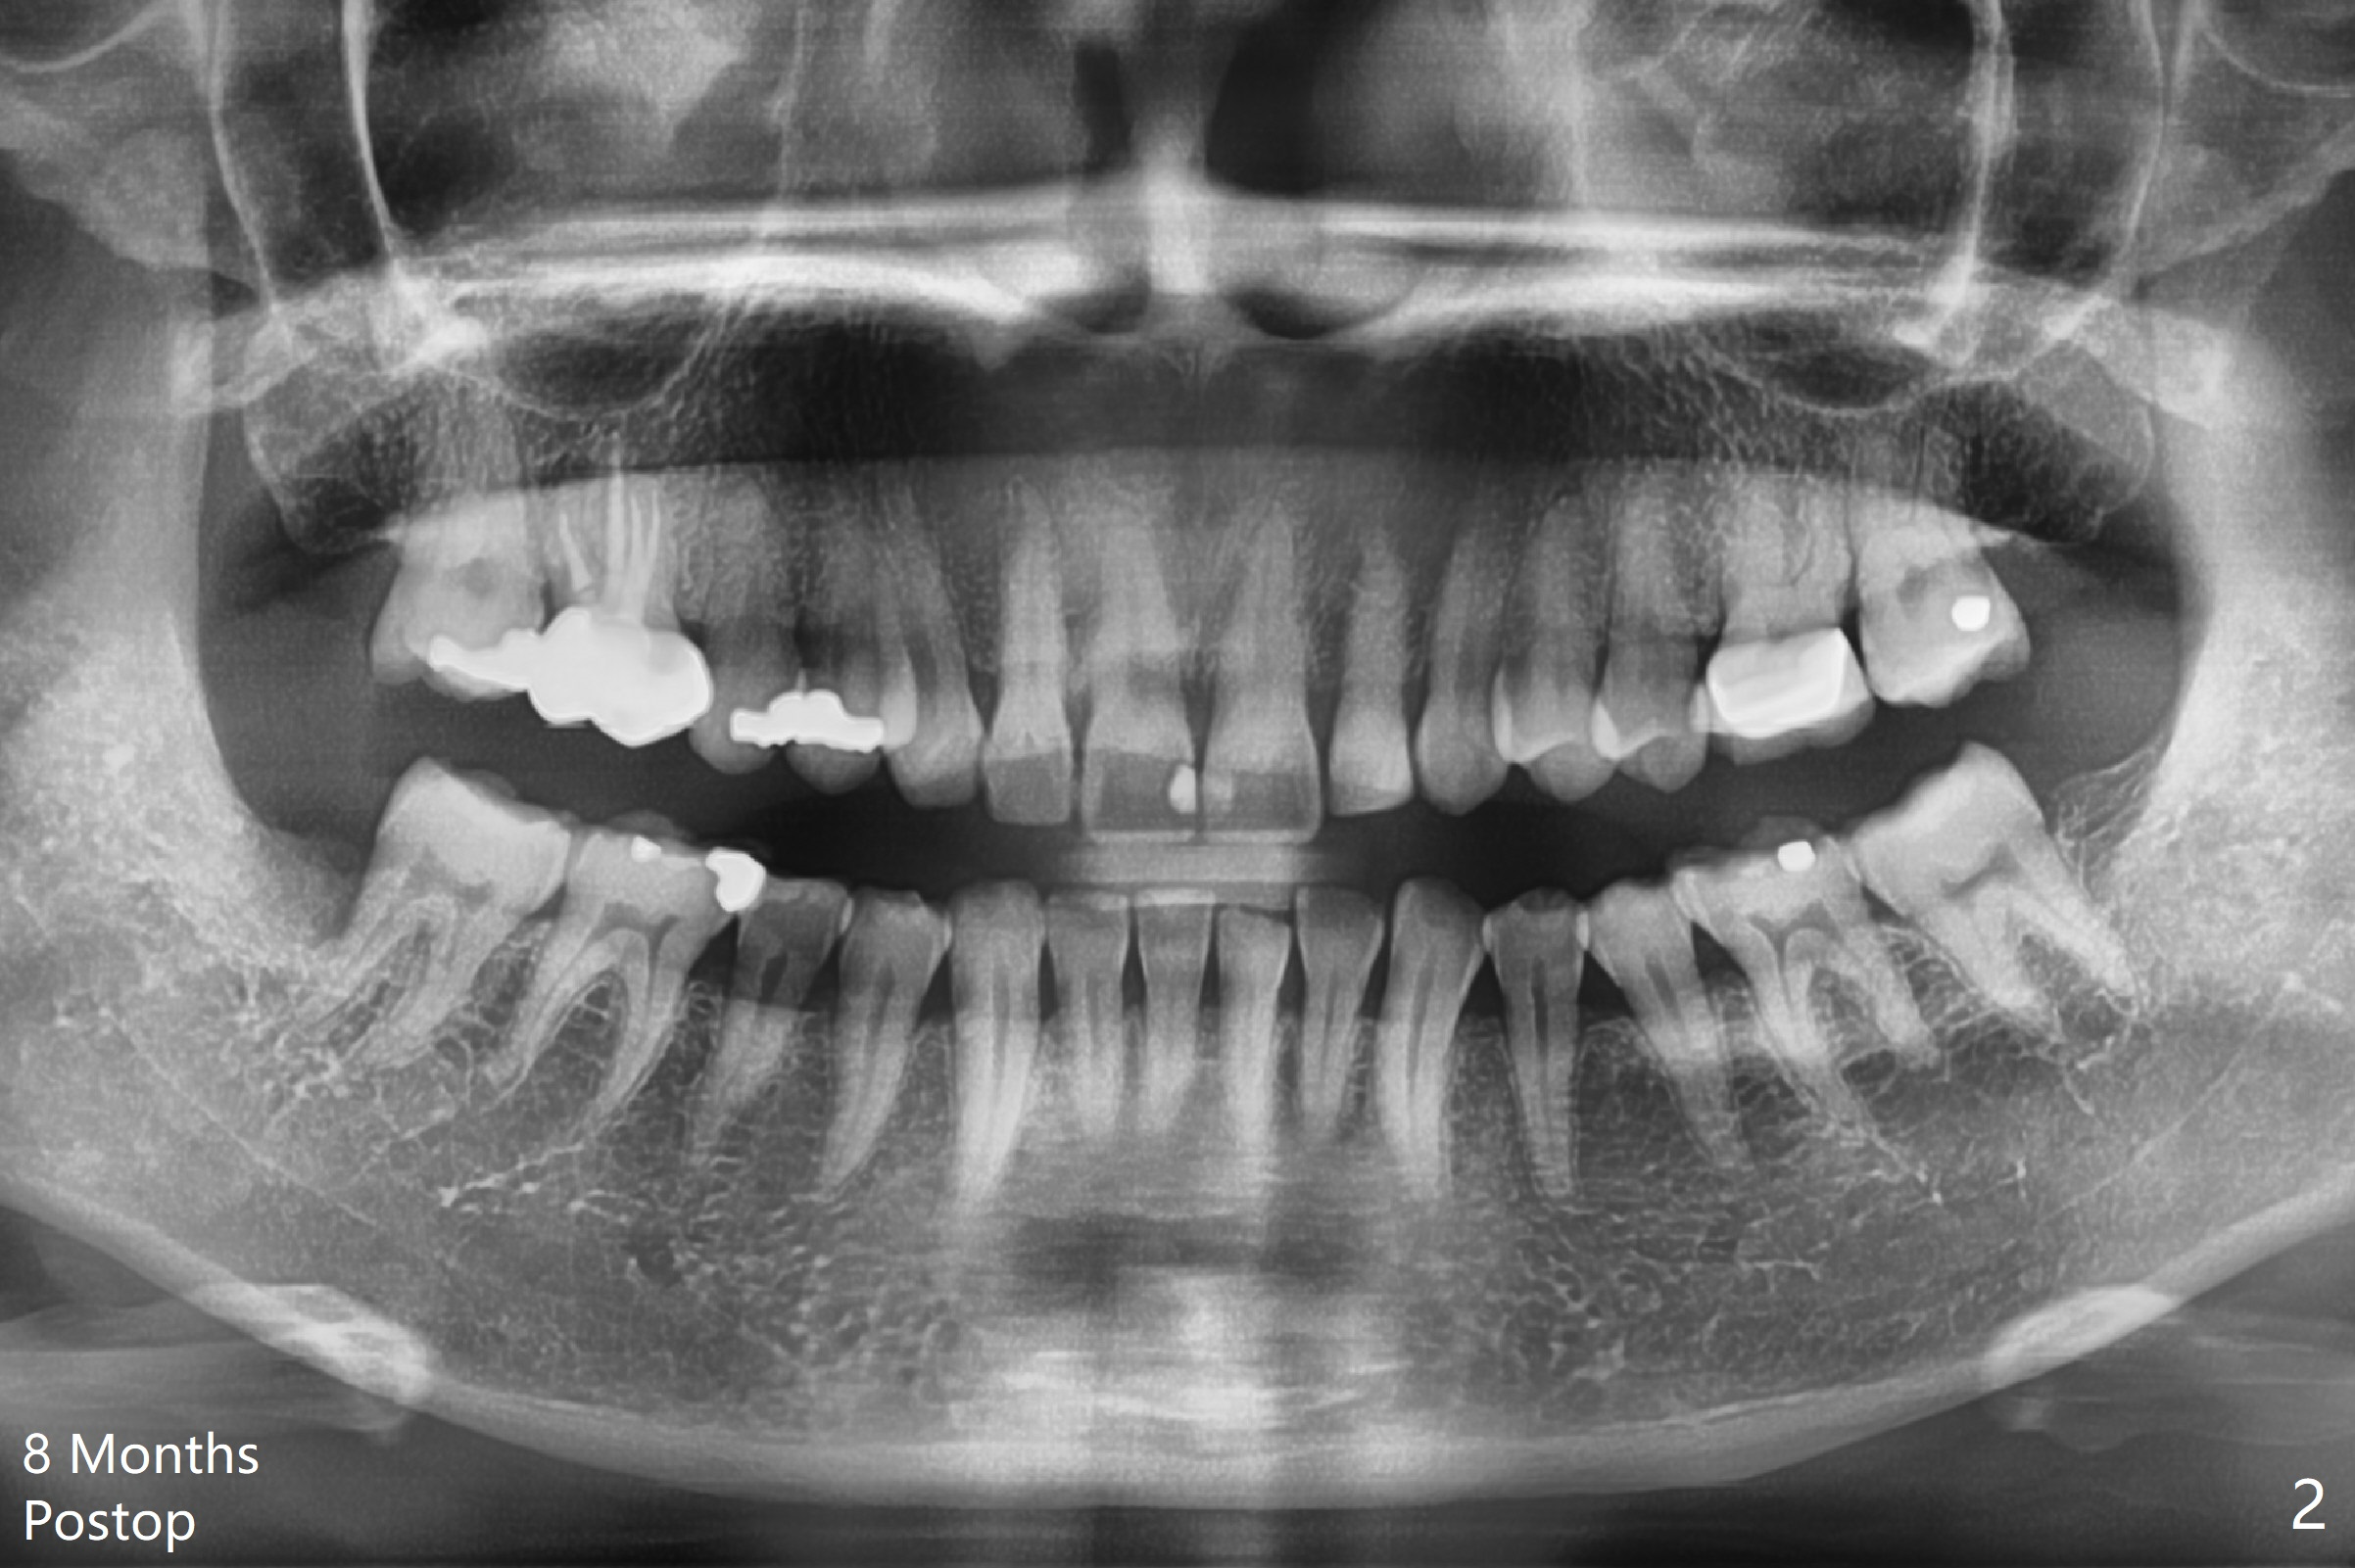

8-Month Follow Up

A 52-year-old woman requests extraction of the tooth #32 (Fig.1). With Local anesthesia, hockey-stick incision is made, reflected mucoperiosteal flap, buccodistal trough, sectioned, straight elevator/forceps removal, curette, Piezo 31 distal, copious irrigation, placed a 10x20 mm OsteoGen Plug into bony defect, 4-0 plain gut suture, 2x2 gauze, hemastatic. The wound heals with apparent bone formation 8 months postop (Fig.2).